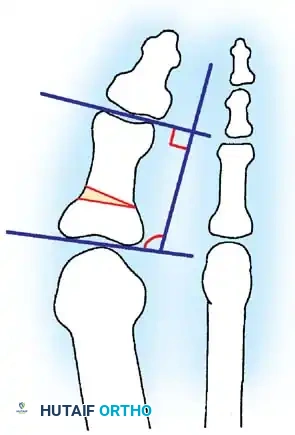

Inadequate vascularity or sensibility should be investigated thoroughly before bunion surgery is considered. In addition, the position of the articular surface of the metatarsal head in relation to the longitudinal axis of the fi rst metatarsal should be determined (Fig. 78-8). Standard preoperative radiographs should include standing dorsoplantar and lateral views, a nonstanding lateral oblique view, and axial sesamoid views (Fig. 78-9). The hallux valgus angle and the fi rst-second intermetatarsal angle should fi rst be drawn on the standing dorsoplantar view by bisecting the shafts of the bones (Fig. 78-10), with an awareness of the normal ranges. These angles are most frequently cited as guidelines for treatment decisions, but Donnelly et al. reported that interobserver measurements of the hallux valgus angle varied by approximately 6 degrees and of the intermetatarsal angle by 4 degrees. They cautioned that potential errors in measurement should be considered when these parameters are used to make treatment decisions. The hallux valgus interphalangeus angle and any evidence of degenerative arthritic changes at the fi rst metatarsophalangeal or metatarsocuneiform joints should be documented. Oddities may be present and, if overlooked, may compromise a technically well-done procedure. Mann emphasized that the presence of an os inter-

Fig. 78-8 A, Determination of position of articular surface of metatarsal head in relation to longitudinal axis of fi rst metatarsal. B, Measurement of distal metatarsal articular angle at time of surgery. Markings are at medial and lateral margins of articular surface of fi rst metatarsal head and longitudinal axis of fi rst metatarsal shaft. metatarseum between the bases of the fi rst and second metatarsals might preclude the effectiveness of a soft-tissue procedure alone to provide suffi cient correction of the increased intermetatarsal angle. Likewise, accessory sesamoids and prominent ungual tuberosities at the interphalangeal joint contribute to a painful callus at the tibial side of this joint. An os tibialis externum frequently is associated with excessive hallux valgus interphalangeus. Varus of the fi rst metatarsal might be a signifi cant part of the overall deformity of the foot even with an intermetatarsal angle of less than 10 degrees. Metatarsus varus with a relatively small hallux valgus angle (15 to 20 degrees) may produce signifi cant deformity even though the angles are not excessive. The usefulness of computer-assisted compared with manual measurement of the intermetatarsal angle, hallux valgus angle, and distal metatarsal articular angle is still uncertain. Both methods have closer interobserver and intraobserver correlation in measurement of the intermetatarsal angle and hallux valgus angle than in measurement of the distal metatarsal articular angle. The reliability of either method has such a wide range (5 degrees), however, that measurements of these angles, although useful as a guide, do not provide a completely reliable indication of the magnitude of deformity. Condon et al. suggested that the reliability of the intermetatarsal angle can be improved by careful technique and by making the measurements at least twice and averaging them. Schneider et al. reported two methods of determining angular measurements based on distinctly different reference points: (1) a longitudinal axis of the fi rst metatarsal using middiaphyseal reference points, and (2) a center-head technique using a center head (center of the articular surface) and center base

(center of the proximal diaphysis) as reference points. They found that measured correction of the hallux valgus and intermetatarsal angles varied by approximately 9 degrees depending on which reference points were used. Recommendations of Coughlin, Saltzman, and Nunley (American Orthopaedic Foot and Ankle Society Ad Hoc Committee on Angular Measurements) included standardized radiographic technique, specifi c placement of reference points (Fig. 78-11), use of a protractor rather than a goniometer for measurements, and, after distal osteotomies, dual measurements using a center-head technique and a Mose sphere.